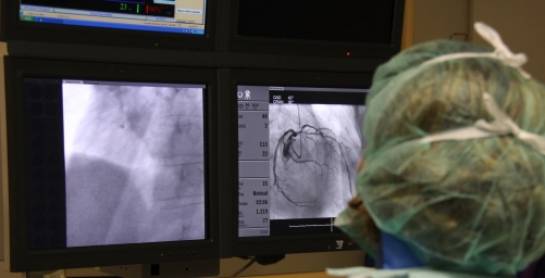

A l'Institut del Cor Teknon comptem amb tecnologia de diagnòstic d'última generació i podem oferir els tractaments més eficaços per solucionar els problemes del vostre cor: angina de pit, infart de miocardi, lesions de les vàlvules cardíaques, insuficiència cardíaca, arrítmies, hipertensió arterial, etc.

Una història clínica detallada i la realització de proves de diagnòstic seran claus per obtenir una informació completa sobre com resoldre el seu problema cardiovascular, obtenint informació sobre l'anatomia, la fisiologia i la funció del múscul cardíac. En aquest sentit, les tècniques de diagnòstic en cardiologia van des del bàsic i tradicional electrocardiograma, totes les modalitats d'ecocardiograma i les proves d'esforç, i les més modernes i noves tècniques com la ressonància magnètica cardíaca i la TAC coronària DMD.